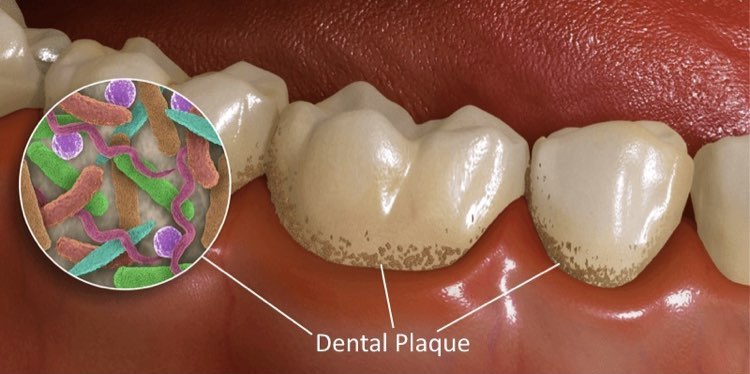

牙菌斑的六大危害

牙菌斑会导致龋齿、牙周病等口腔疾病。但是牙菌斑呈白色或浅浅的黄色,不容易被发现和重视。